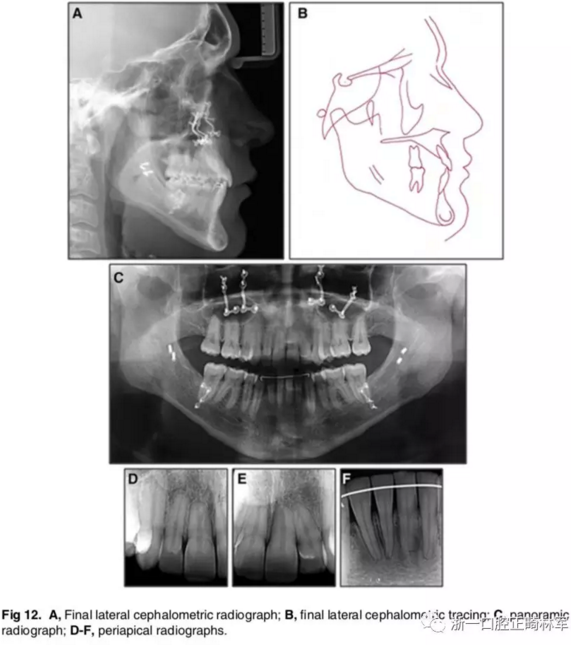

影像學:全景片示:牙根平行度可。頭顱側(cè)位片及疊加圖示:顯著的骨性、牙性改變;其中,最大的改變?yōu)樯舷骂M位置關(guān)系,改變了7mm;由此帶來的改變?yōu)锳NB角從-4°變?yōu)?°,Wits值由-10mm變?yōu)?1.5mm,上頜突度減?。ˋ-NPer,3mm),上下頜不調(diào)改善(Co-A-Co-Gn,41mm),從而使側(cè)貌更為平直;下頜磨牙遠中移動,無伸長、傾斜,反映了下頜整體的遠中移動;上下切牙傾角糾正(1:NA,7mm、25°; 1:NB,4.5mm、20°; IMPA,78°),從而改善了在基骨中的位置。

功能:前伸合的切牙引導(dǎo)與側(cè)方合的尖牙引導(dǎo)得以實現(xiàn)。

側(cè)貌:上唇突度增大4mm(至S線0mm),整體側(cè)貌更為和諧。

5年隨訪:治療結(jié)果保持穩(wěn)定,無明顯復(fù)發(fā),但下頜中線有輕微偏移;下頜磨牙位置始終保持穩(wěn)定。